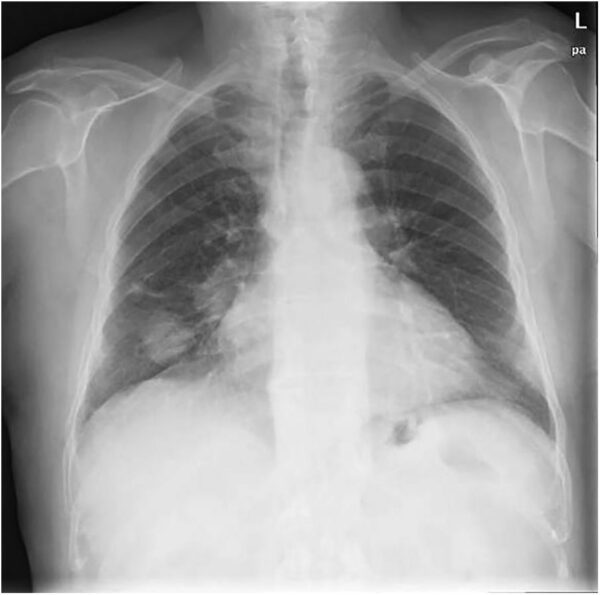

Diagnóstico de carcinoma broncogénico

El cáncer de pulmón constituye actualmente la primera causa de mortalidad oncológica a nivel mundial tanto en varones como en mujeres, fenómeno que obedece a una confluencia de factores biológicos,…